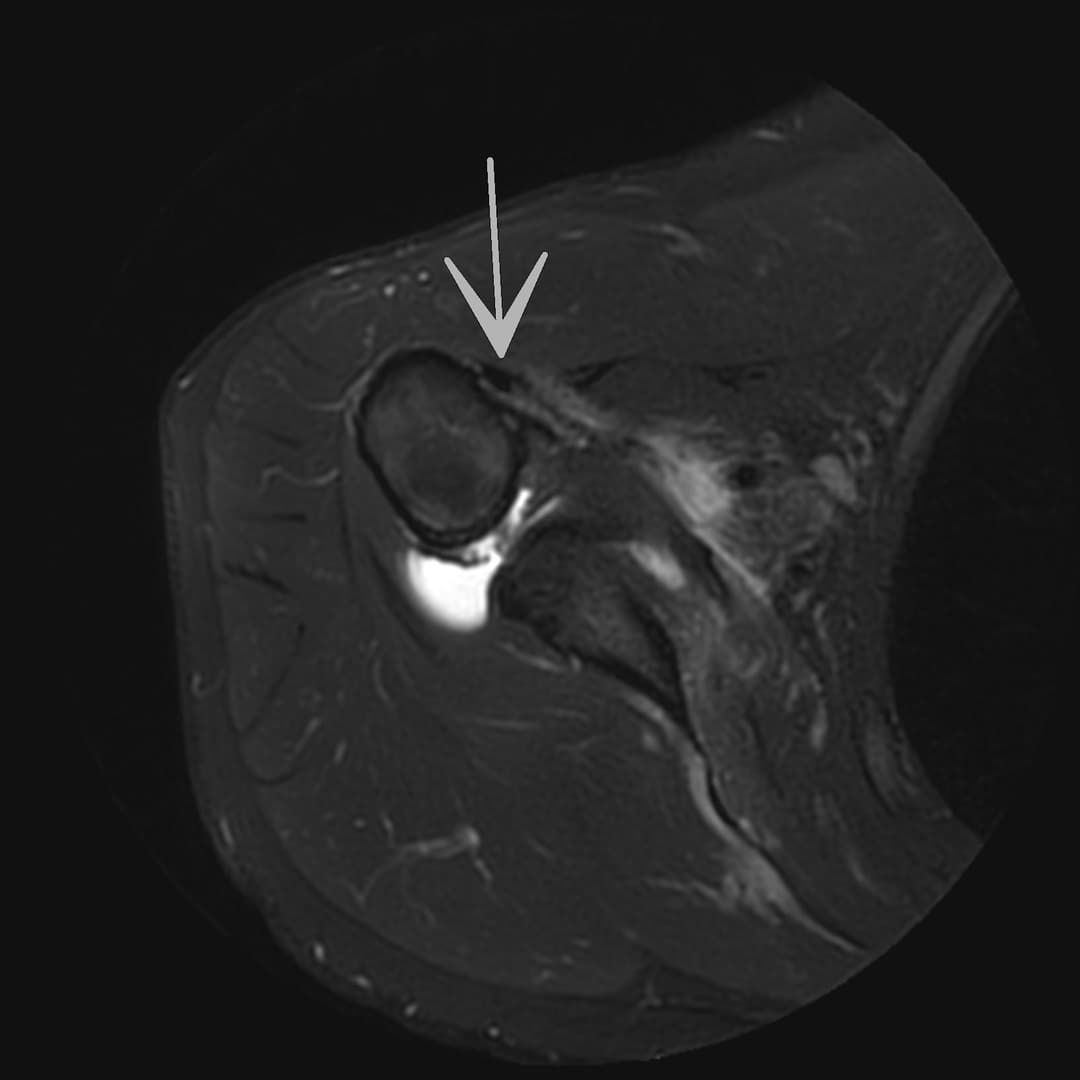

Rupture du tendon sous-scapulaire

IRM

Ténodèse du long biceps intacte. Tendons sus et sous épineux respectés. Large diffusion du contraste depuis compartiment articulaire vers la BSAD.

Rupture du tendon sous-scapulaire avec rétraction grade II-III